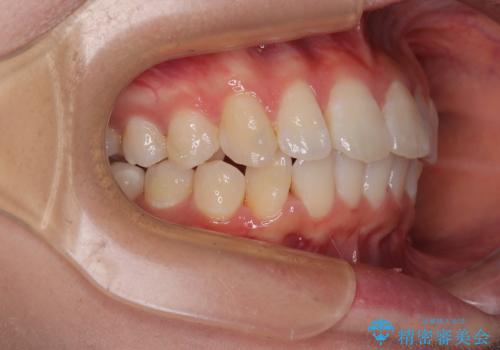

深い咬み合わせによる隙間 インビザライン矯正でコンプレックスを改善

- 上の前歯の隙間を気にして来院された患者様です。

インビザラインにより、上下の歯列を側方に拡大しつつ、前歯の隙間を閉じていくこととしました。

隙間の原因は強い咬合力や舌の突出癖、小帯の異常付着などがありますが、舌のトレーニングをしっかりと行いながら、装着時間を遵守して装着していただいたおかげで、スムーズに治療を終えることができました。